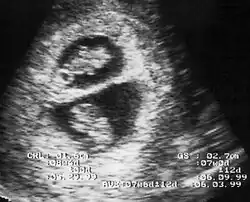

λ Sign in 8 week pregnancy

By performing an obstetric ultrasound at a gestational age of 10–14 weeks, monochorionic-diamniotic twins are discerned from dichorionic twins. The presence of a "T-sign" at the inter-twin membrane-placental junction is indicative of monochorionic-diamniotic twins (that is, the junction between the inter-twin membrane and the external rim forms a right angle), whereas dichorionic twins present with a "lambda (λ) sign" (that is, the chorion forms a wedge-shaped protrusion into the inter-twin space, creating a rather curved junction).[4] The "lambda sign" is also called the "twin peak sign". At ultrasound at a gestational age of 16–20 weeks, the "lambda sign" is indicative of dichorionicity but its absence does not exclude it.[5]